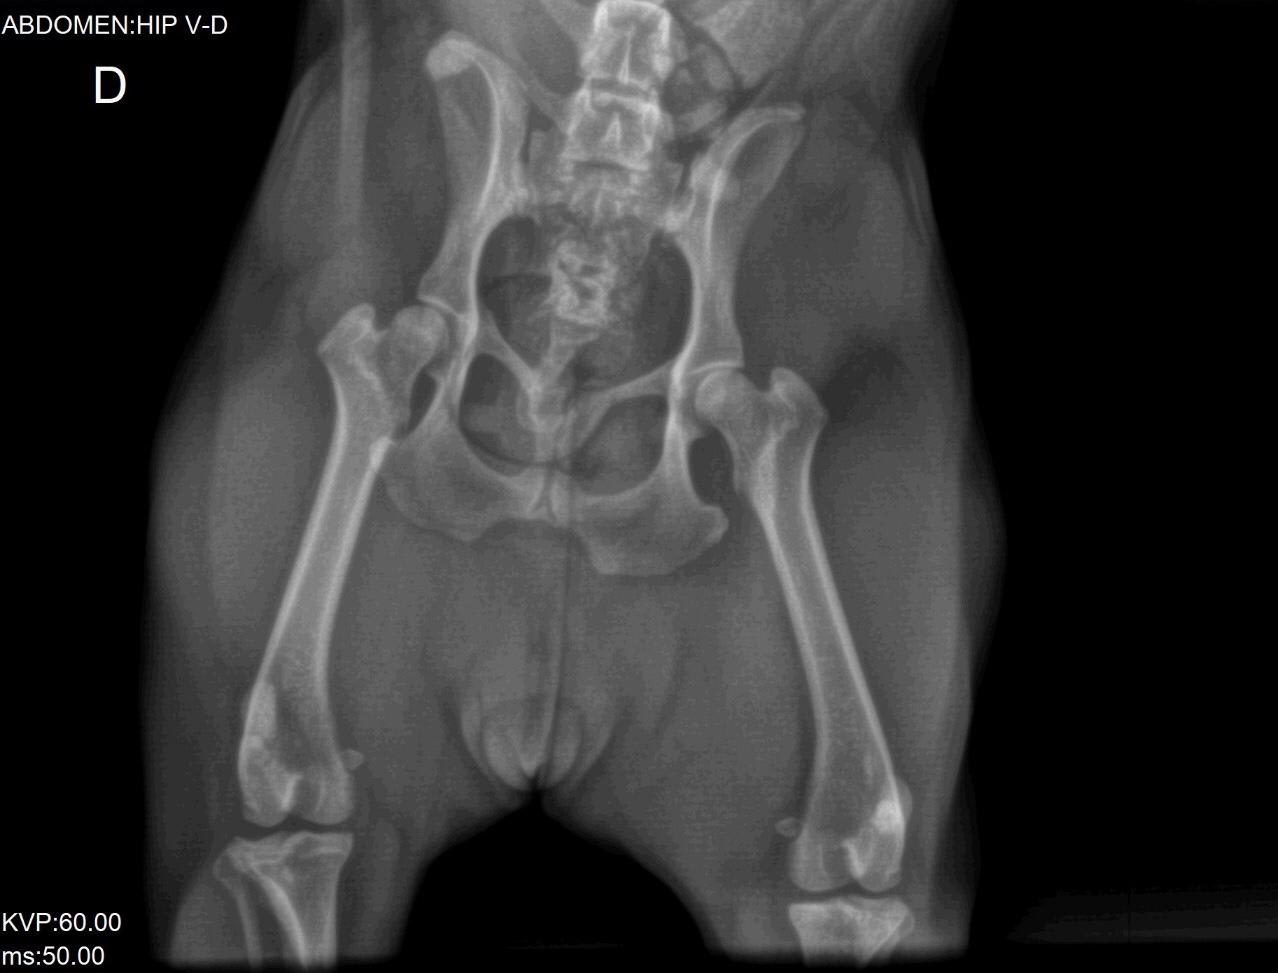

Our 2 year old french bulldog has been shivering from time to time since one week ago. We took her to the vet but want a second opinion. See images attached. We would appreciate your comments.

The hips look ok (hip dysplasia is possible on the right hip joint, but the positioning isn't perfect, which is required for that diagnosis). She does have significant issues with the vertebrae in her thoracic spine. I cannot tell exactly what is going on from these x-rays (it is much easier to evaluate them in-person), but they are likely causing significant discomfort. Lulu may need pain medications for life. A second opinion from a veterinary orthopedic surgeon would be a good idea to see if there is a surgical option to provide pain relief.